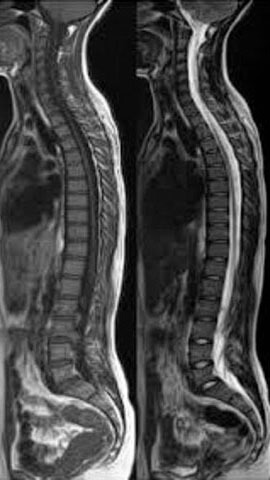

MRI 検査(Magnetic Resonance Imaging / 磁気共鳴映像法) とは、電磁石のトンネルの中に身体を入れ、磁気と電波 を使用して、身体の中の断面写真を得る検査です。現在、一般に使用されている画像診断法であるエックス線撮影やCT検査ではエックス線を使いますが、MRI検査では磁気と電波を使いますので、放射線被ばくの心配がありません。 また、身体の輪切り(横断面)の写真だけでなく、あらゆる角度の断面の写真を得ることができ、病気の部分の診断にたいへん役に立つ精密検査です。

全脊椎[※注意] 心臓ペースメーカー・金属制心臓人工弁や刺激電極などを身につけている方のMRI検査はできません。